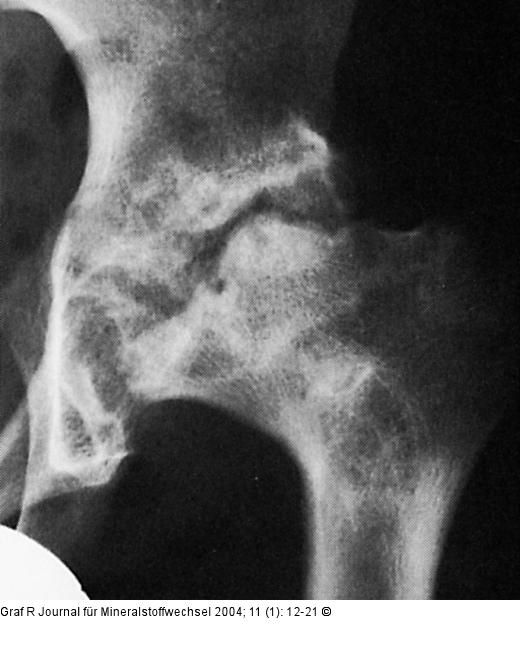

Abbildung 6: Hüftgelenk Morbus Perthes: Das Hüftgelenk weitgehend zerstört, der Hüftkopf nur mehr in Resten vorhanden und entrundet. |

Morbus Perthes: Das Hüftgelenk weitgehend zerstört, der Hüftkopf nur mehr in Resten vorhanden und entrundet. |